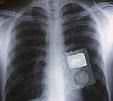

滋賀県の琵琶湖大学病院で今年2月に肺の手術をして無事完了した。 所が最近、喉の奥に違和感を感じた

喉の奥から、何か音楽が聞こえる

病院に行って検査をすると、なんとiPodが

しかし無事... 続きを読む